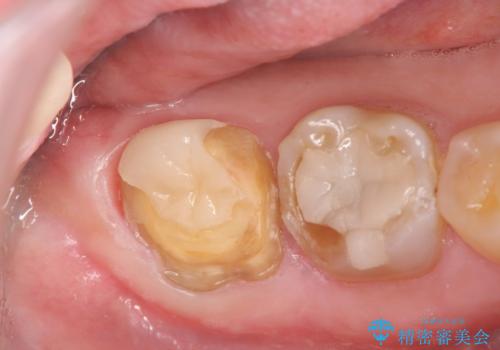

歯ぎしりによる異常に低い歯冠高径 歯周外科による解決

歯周外科を行い歯茎の位置を下げることで安定したクラウン製作ができる状態を目指します。

あまりにもクラウン高径が低いと、安定性が悪くなりセメントの溢出を招き虫歯の再発リスクを高めます。